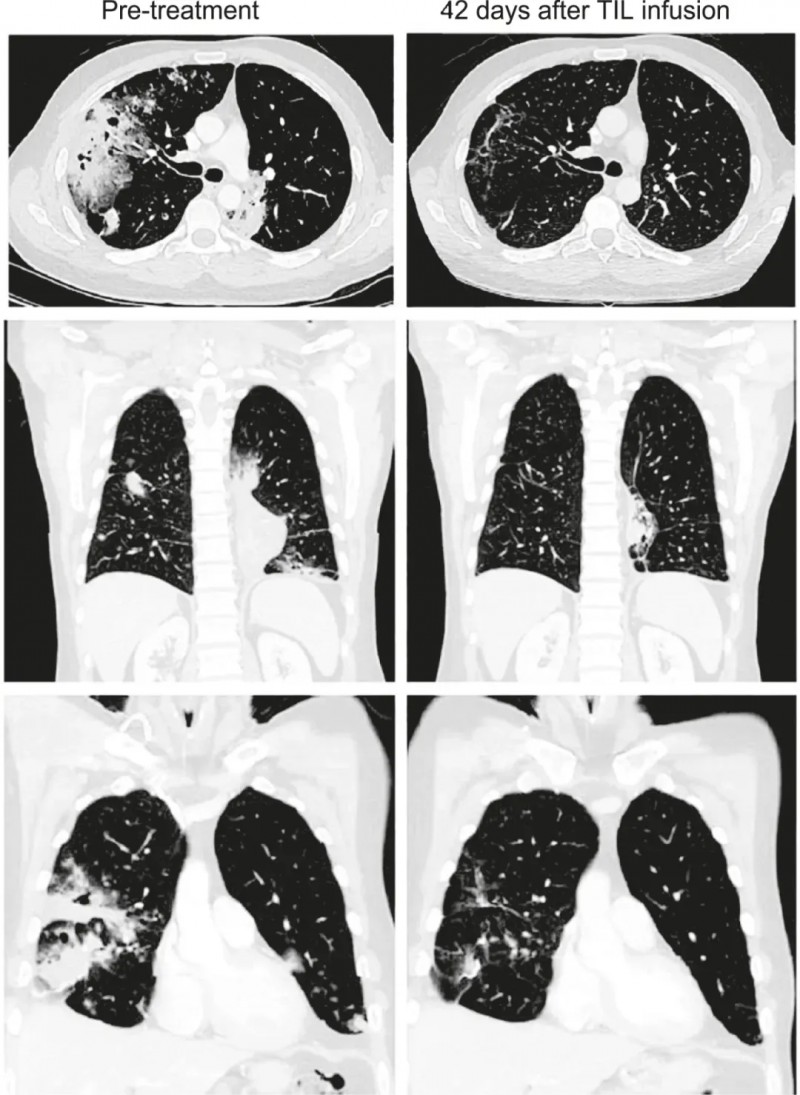

值得一提的是,其中一位41岁的携带KRAS G12D突变的IV期粘液性肺腺癌男性患者,TMB为3.3mut/Mb,PD-L1表达为0%。输注TIL后12周,根据RECISTv1.1标准及CT扫描结果显示,该患者部分缓解(PR)率竟高达81%(详见下图)。

▲图源“Cancer Discov”,版权归原作者所有,如无意中侵犯了知识产权,请联系我们删除